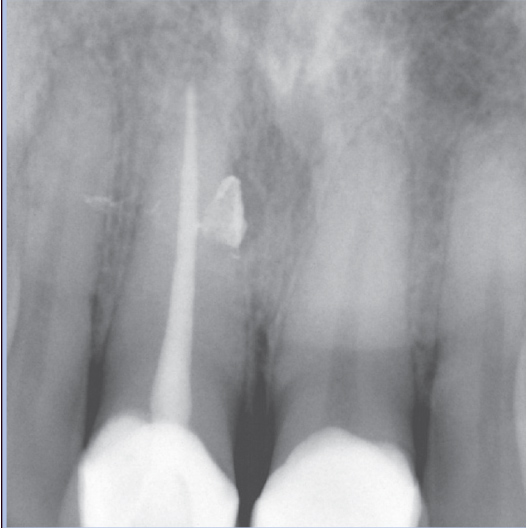

Before

Before Root Canal treatment